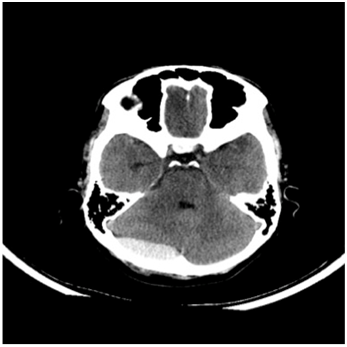

This led to the formulation of our criteria for PFEDH management, as shown below (Table 2). All bleeds greater than 4cms in horizontal diameter were taken up for surgery (Figure 6). For bleeds smaller than 4cms, GCS was employed as the deciding criterion, where patient with low GCS despite small bleeds were taken up for decompression and hematoma evacuation, while better GCS patients were observed (Figure 7).

Figure 6 Large posterior fossa extradural bleed,Operative group.